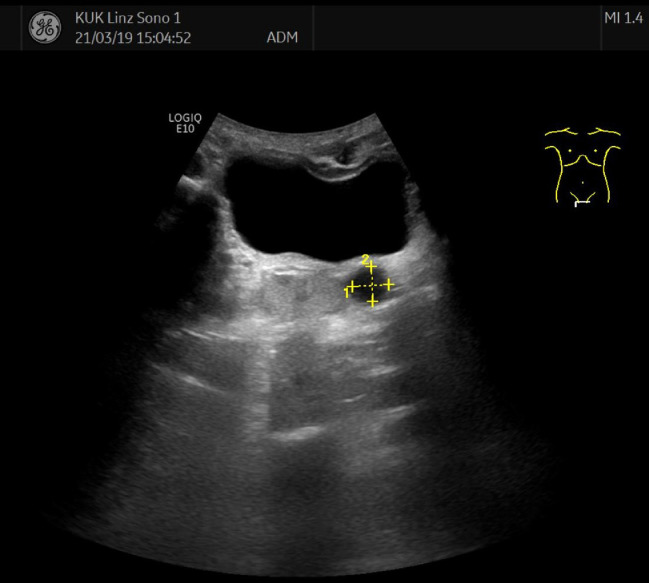

The thoracic CT revealed extensive bilateral pulmonary embolism with accompanying pleural effusion on the left side and infarct pneumonia in the left lower lobe (Fig. 1) The deep vein sonography showed normal findings without evidence of deep vein thrombosis. Sonography of the abdomen revealed left renal agenesis as well as a cystic structure on the left side adjacent to the prostate with 1.3 cm in size (Fig. 2).

Fig. 2.

Sonography of the abdomen showing a cystic lesion, 1.3 cm in size, close to the bladder and the prostate additionally to left renal agenesis.